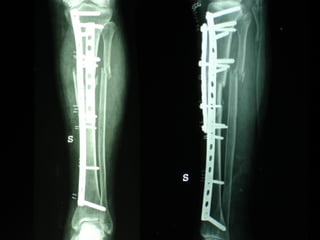

Dal Gennaio 2000 al Febbraio 2006 abbiamo trattato 167 fratture chiuse  con placca percutanea  in 164 pazienti :  27 lesioni diafisarie di gamba, 12 piloni tibiali ,  11 fratture prossimali di tibia, 36 fratture sovracondiloidee di femore, 17 fratture diafisarie di femore, 43 fratture metaepifisarie prossimali di omero, 21 diafisarie d’omero.  156 guarigioni 8 fallimenti

I buoni risultati ottenuti dipendono da 5 punti fondamentali:   una accurata riduzione percutanea della frattura  precise vie di accesso  l’utilizzo della placca che consenta il più lungo braccio di leva possibile il pretensionamento della placca  una sintesi con un ridotto numero di viti

Precise vie di accesso

Placche lunghe e pretensionate

Placche lunghe e pretensionate Sintesi con un ridotto numero di viti